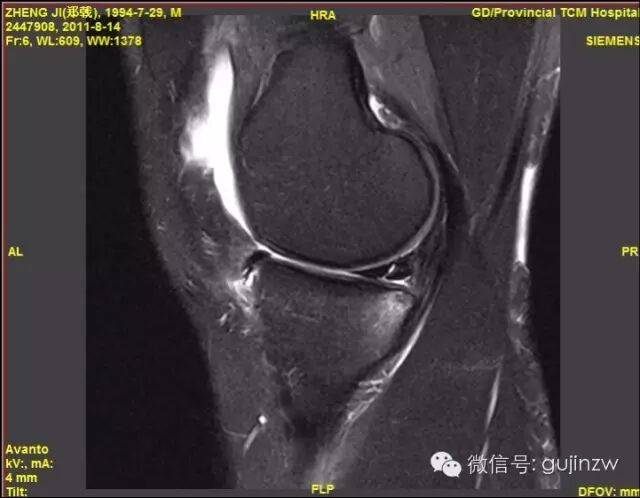

MRI